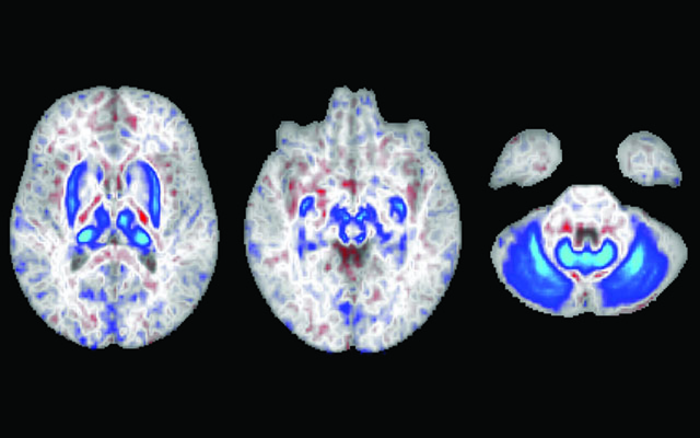

在這些腦部掃描中,藍色區域表示有兩個血色素沉著癥風險基因的個體中鐵積聚的區域。這些區域也在運動中發揮作用。

但在《JAMA Neurology》2022年8月1日在線版上發表的一項新研究中,加州大學圣地亞哥分校的研究人員與加州大學舊金山分校、約翰霍普金斯大學彭博公共衛生學院和Laureate大腦研究所的同事報告稱,擁有兩份基因突變副本(從父母雙方各繼承一份)的個體顯示,大腦負責運動的區域有大量的鐵積聚。研究結果表明,主要導致遺傳性血色素沉著癥的基因突變可能是導致運動障礙的危險因素,比如帕金森病,它是由產生化學信使多巴胺的神經細胞的缺失引起的。

根據美國疾病控制與預防中心(Centers for Disease Control and Prevention)的數據,這項觀察性研究包括對836名參與者進行核磁共振掃描,其中165人有患上遺傳性血色素沉著癥的高風險,大約每300名非西班牙裔白人中就有1人患此病。掃描發現這些高危人群大腦運動回路中有大量鐵沉積。然后,研究人員分析了近50萬人的數據,發現血色素沉著癥的遺傳風險高的男性,而不是女性,患運動障礙的風險增加了1.8倍,其中許多人沒有同時被診斷為血色素沉著癥。